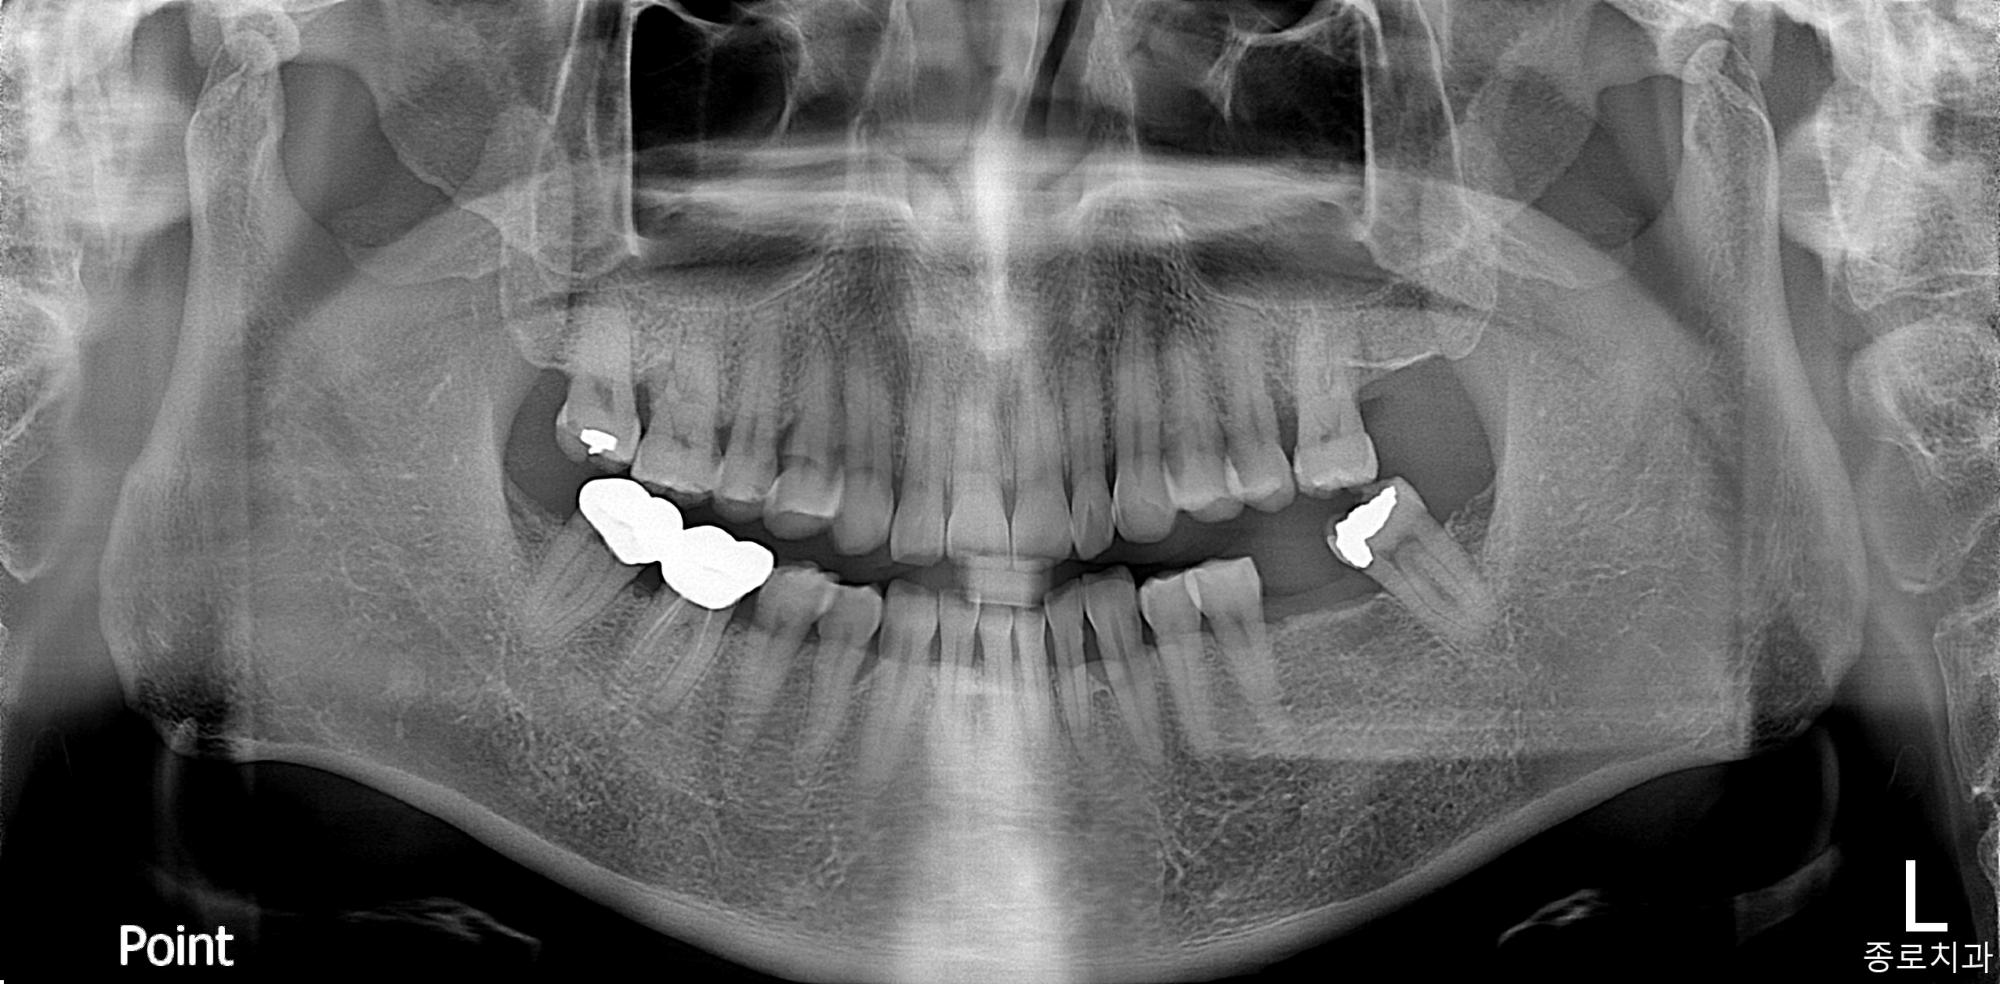

전/후 사진갤러리